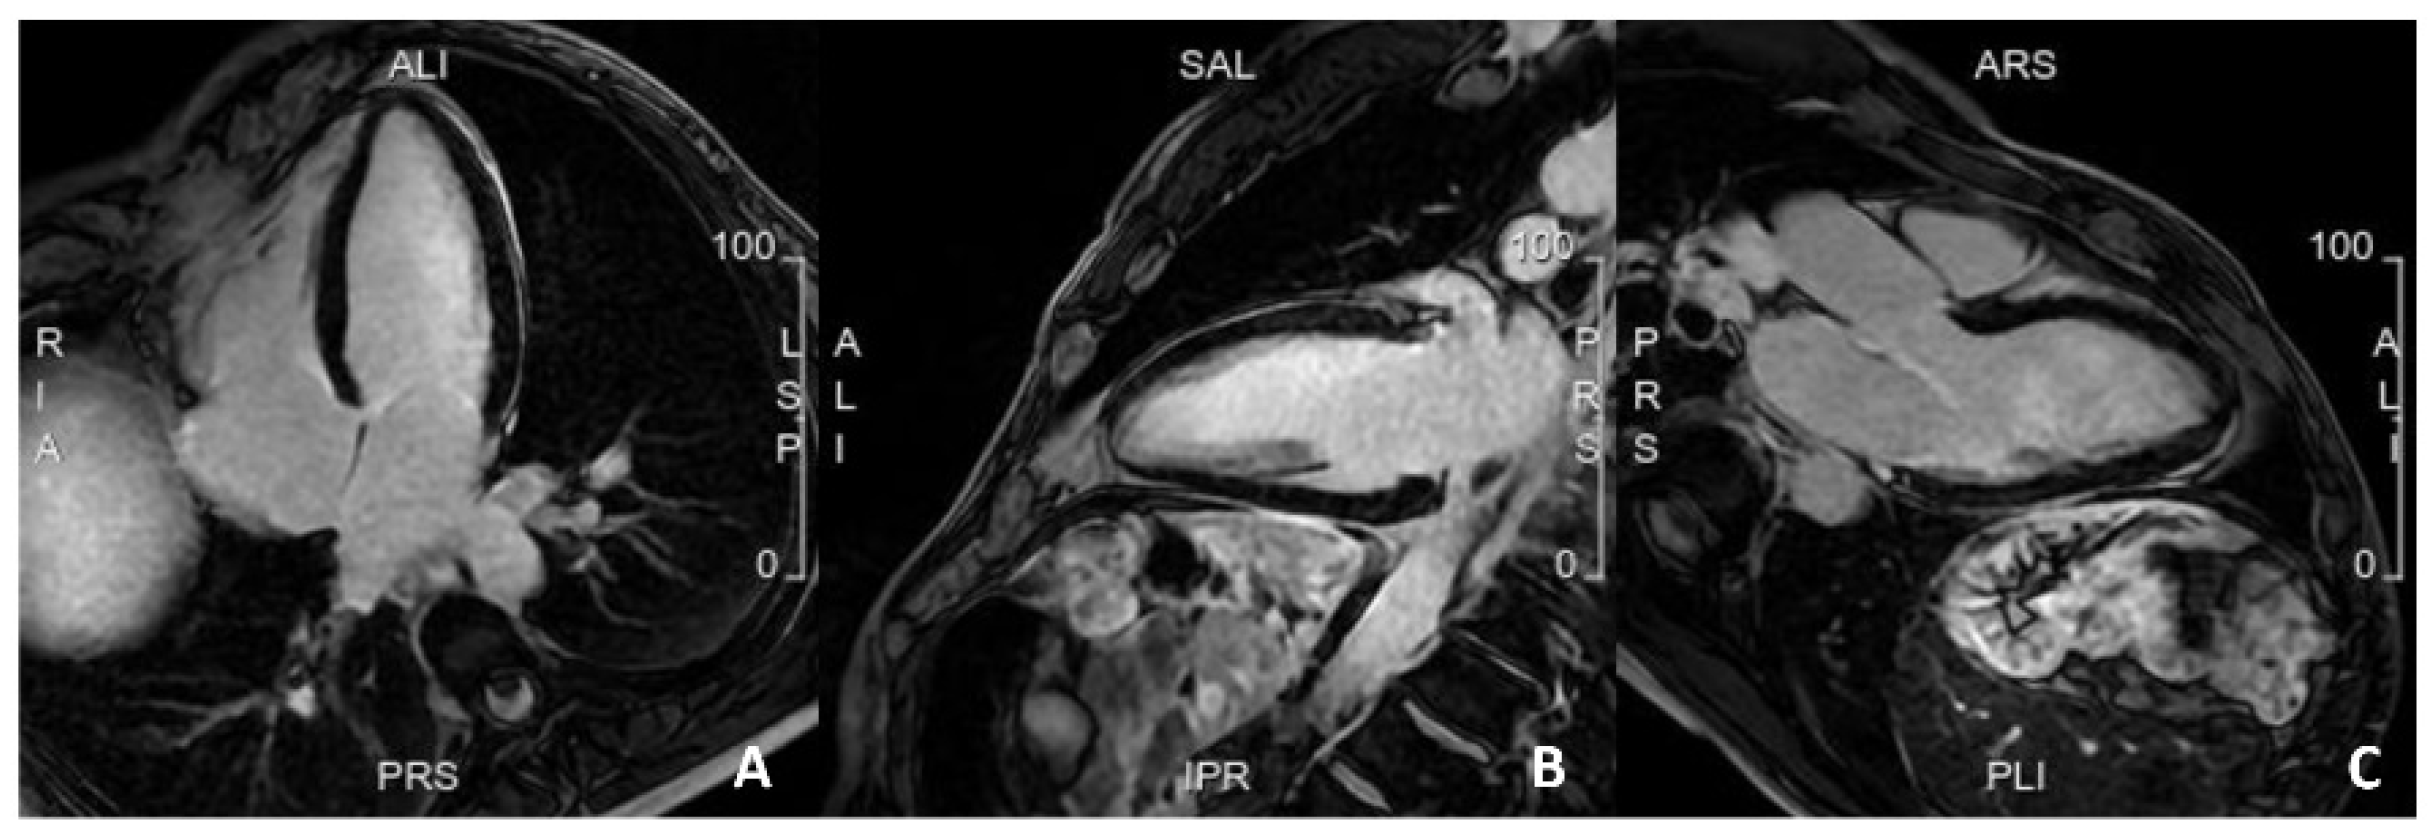

Figure 6.

A case from a patient with a recent myocardial infarction. Cardiac MRI evidenced the presence of extensive myocardial left ventricular fibrosis associated with worse prognosis at follow-up.